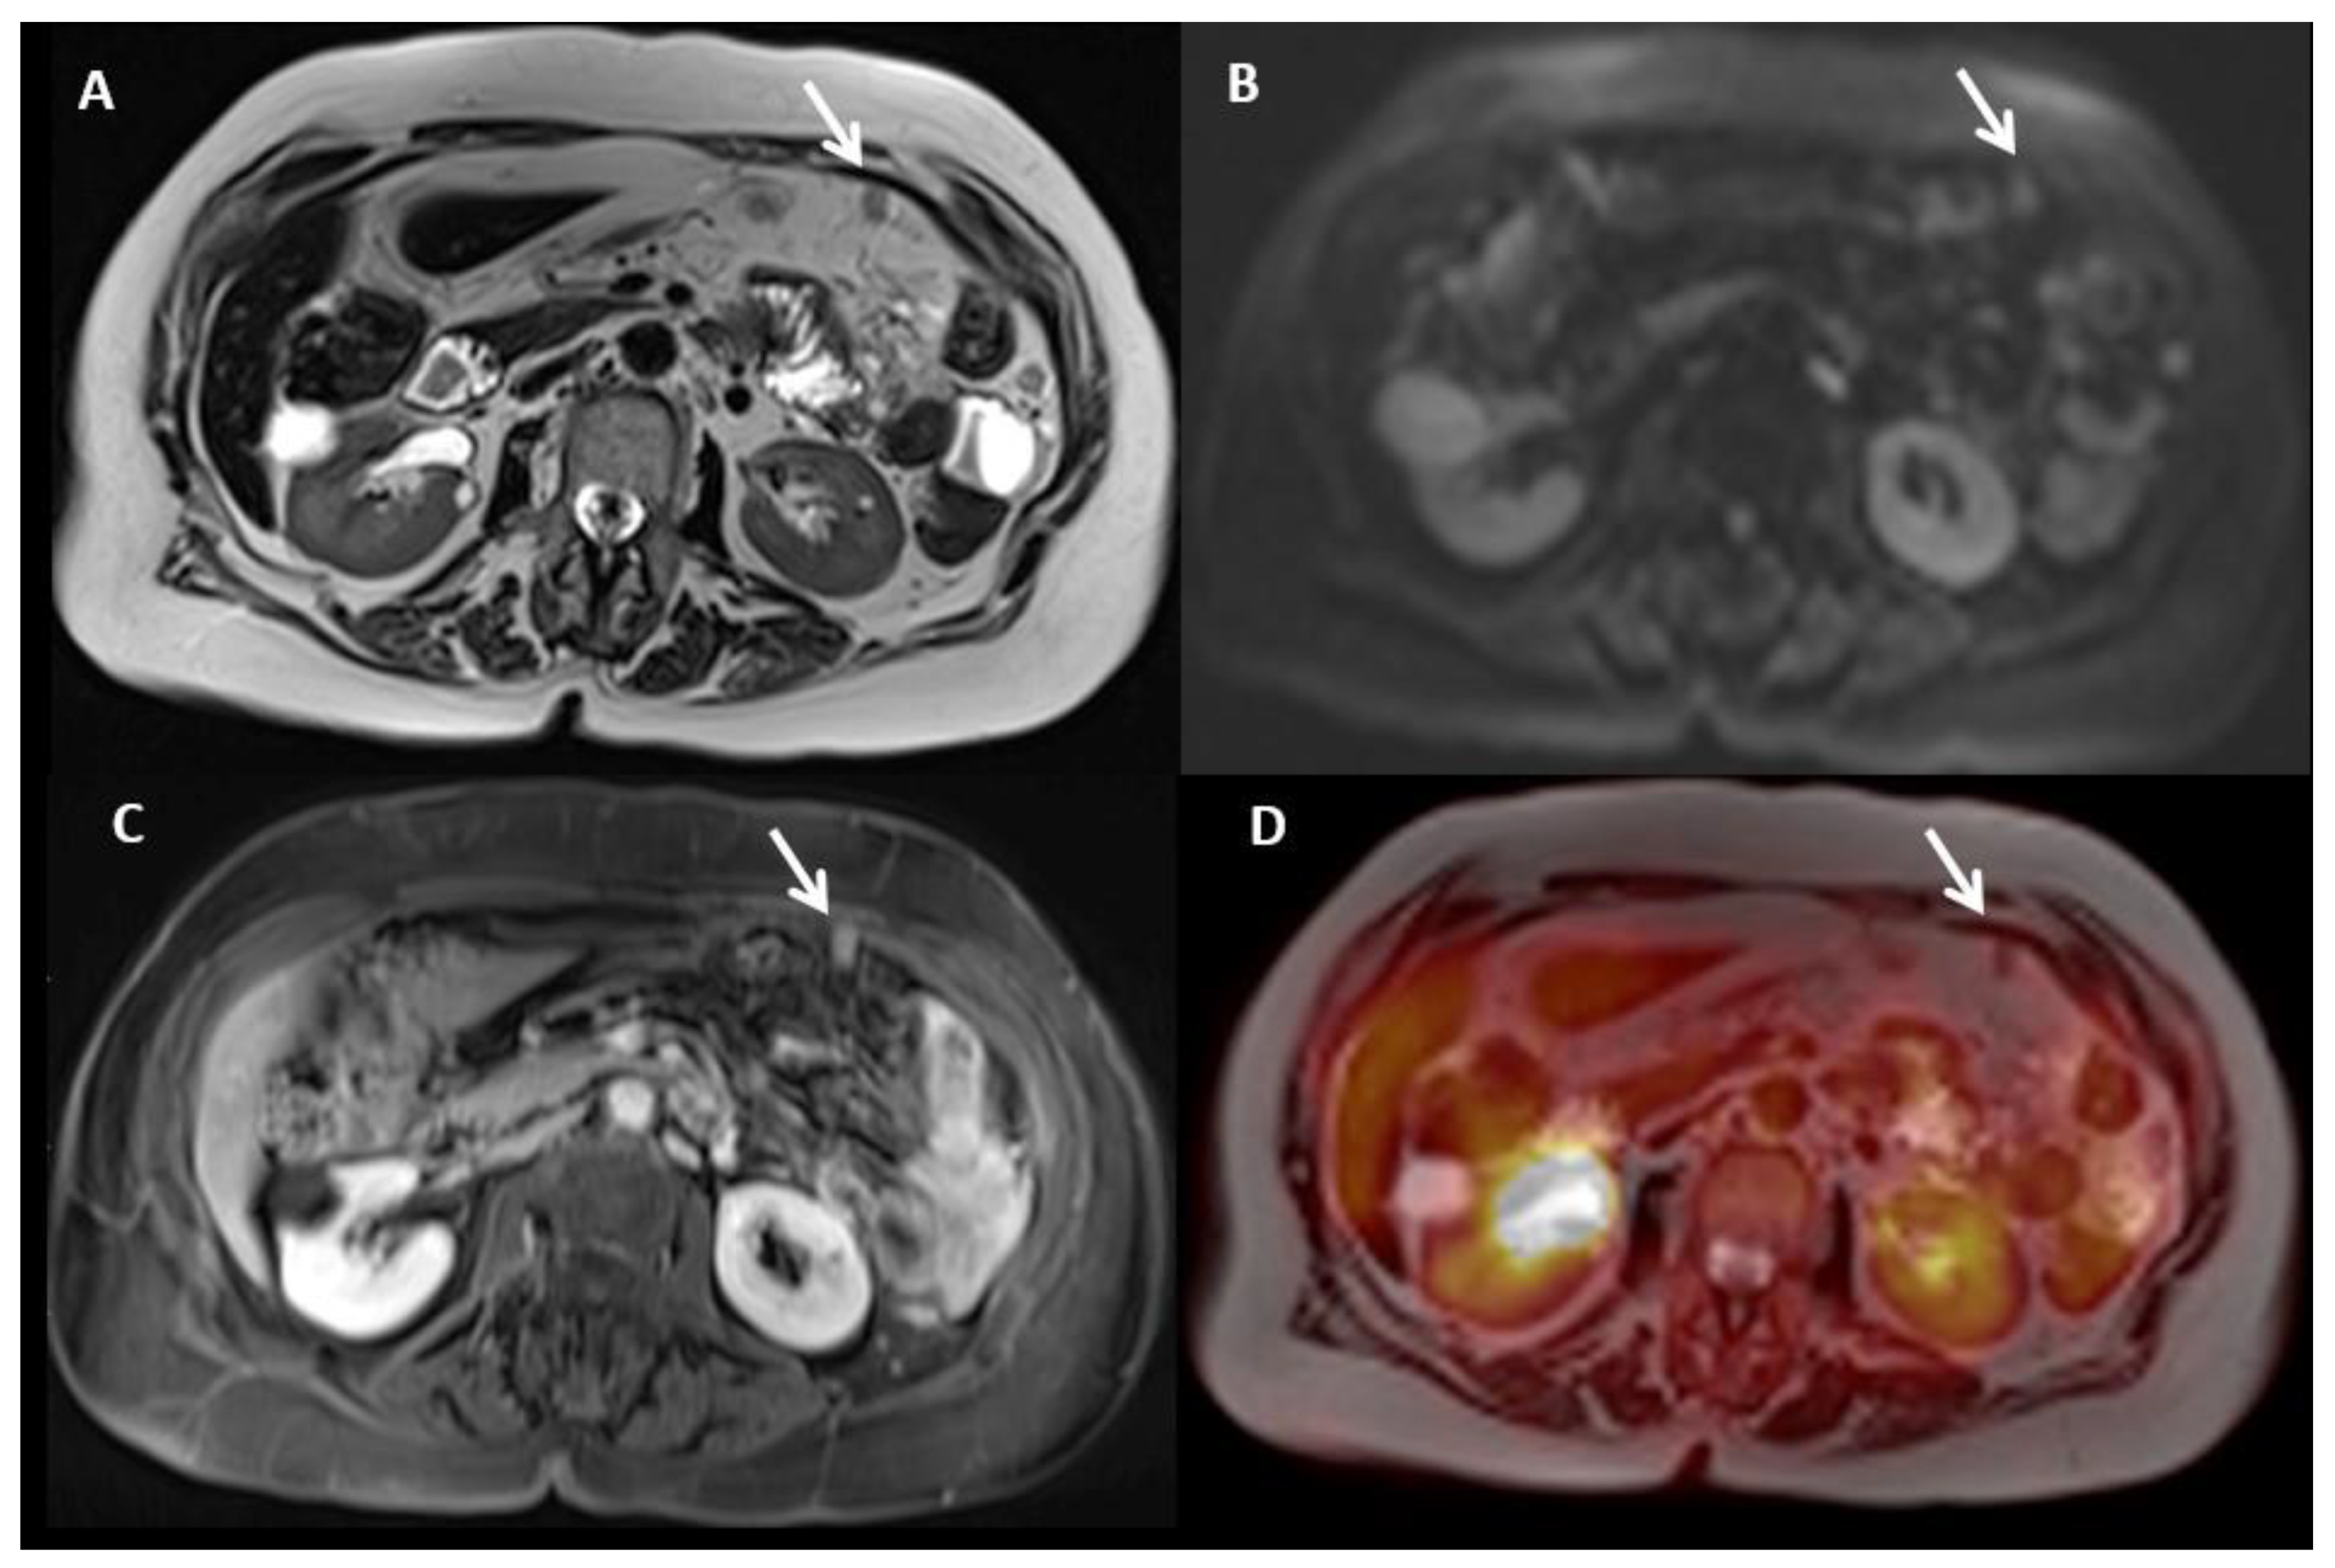

- Jónsdóttir, B.; Ripoll, M.A.; Bergman, A.; Silins, I.; Poromaa, I.S.; Ahlström, H.; Stålberg, K. Validation of 18F-FDG PET/MRI and diffusion-weighted MRI for estimating the extent of peritoneal carcinomatosis in ovarian and endometrial cancer -a pilot study. Cancer Imaging 2021, 21, 1–10. [Google Scholar] [CrossRef] [PubMed]